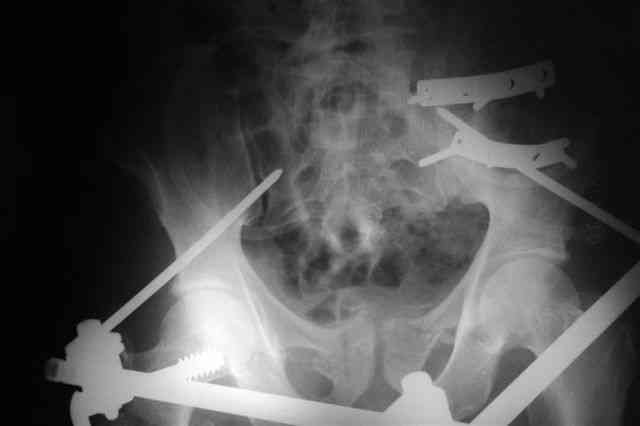

Вчера прооперировал больного.

Попытка низвести половину таза на тракционном столе ( скелетное вытяжение за бедро) безуспешная.

из переднего доступа добрался до правого КП сочленения , все запаяно костью, с помощью 2 шанцев винтов в крестец и подвздошную кость и элеватора репозиция, контроль ЭОП

и двумя пластинами фиксация.

Спереди, аппарат как рекомендовал Джолдас.

Снимки плохого качества( очень темные) завтра переделают и пришлю на конференцию.

На мой взгляд, смещение устранено и фиксация выглядит вполне анатомичной.

В приложении послеоперационные картинки.

Всего доброго,

Спасибо всем принявшим участие в обсуждении,

Чекашкин Е.И.